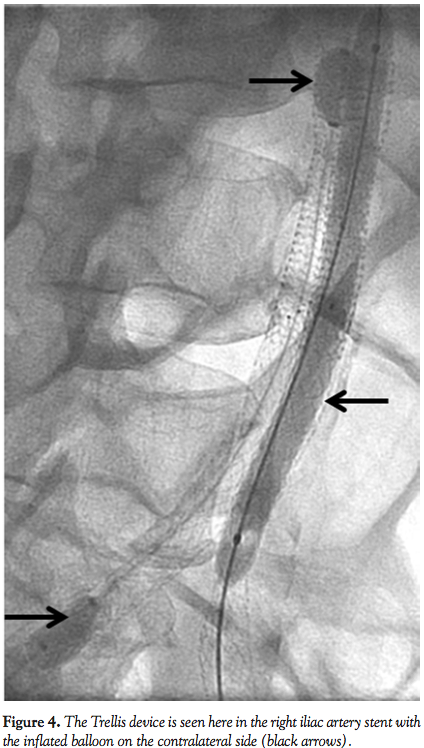

try a retrograde approach using a 6 Fr sheath in the right common femoral artery. The difficulty was due to the fact that our wires kept going into the left iliac through the juxtaposed stents in the distal aorta. It was then decided to use a 10 cm Trellis device for pharmacomechanical thrombectomy. During this, an 8.0 x 120 balloon was inflated in the distal aorta to the left common iliac artery juxtaposed stent to prevent the embolization of thrombus and to keep this isolated to the left lower extremity (Figure 4). A total of 20 mg of tissue plasminogen activator was used with good results, after which kissing-balloon inflation was performed in the distal aorta to the bilateral common iliacs. Final angiogram (Figure 5) showed good flow in bilateral iliac arteries with 3-vessel runoff to both feet.